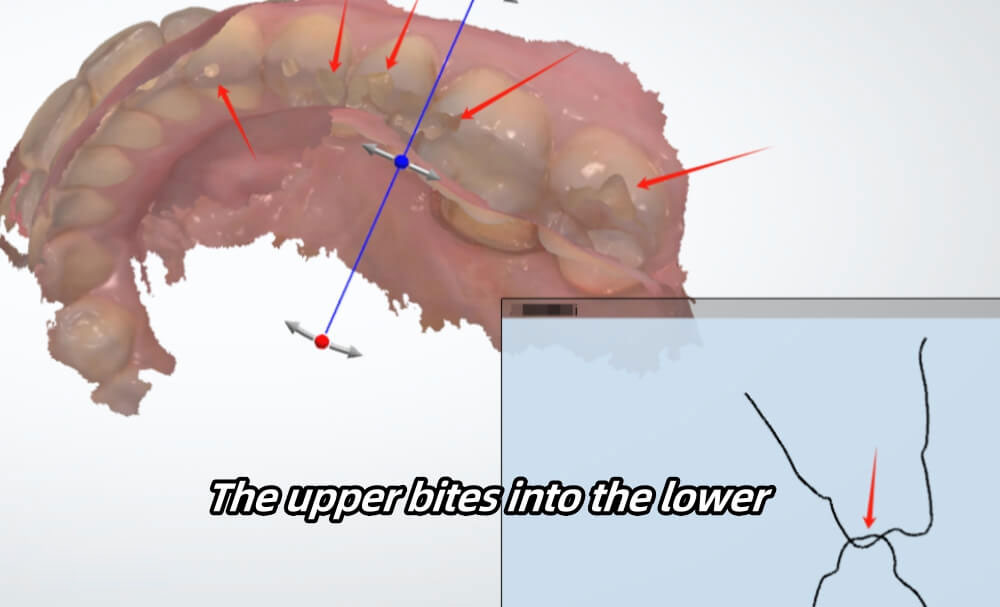

With this case, the upper bites into the lower.